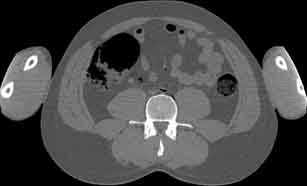

Visible Human male: Sectio transversalis 1702

CT